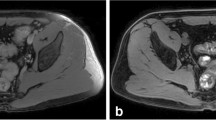

A somewhat different approach for diffusion-weighted imaging is obtained by inserting a single diffusion gradient in a steady-state free-precession (SSFP) sequence. SSFP sequences can be differentiated in three different basic types: those that acquire a free-induction-decay(-FID)-like signal such as the “Fourier-acquired steady-state” (FAST) or “fast imaging with steady precession” (FISP) sequences; those with a spin-echo-like signal such as the contrast-enhanced FAST (CE-FAST) or the reversed FISP (PSIF) sequences; and finally those with fully balanced gradients that acquire a combination of both signals such as the TrueFISP or balanced SSFP (bSSFP) sequences (Oppelt et al. 1986; Bruder et al. 1988; Gyngell 1988). To obtain a reasonable diffusion weighting at short repetition times (TR), particularly the spin-echo-like approaches have proven useful (Le Bihan 1988; Merboldt et al. 1989). Inserting a single (monopolar) diffusion gradient in each TR provides a spin dephasing that is rephased at a later TR (not necessarily at the immediately successive one since the magnetization is switched around between transversal and longitudinal contributions). The delayed rephasing is advantageous in that it provides an increased diffusion weighting—however, it becomes extremely complicated to exactly quantify the diffusion weighting, since it depends not only on the properties of the diffusion gradient, but also on the flip angle, the TR, and the relaxation times of the tissue (Wu and Buxton 1990; Buxton 1993; Deoni et al. 2004). Therefore, diffusion-sensitized SSFP sequences can be used to acquire diffusion-weighted image data (which qualitatively visualize increased ADCs as attenuated signal), but not for the exact quantification of diffusion coefficients. This approach has been demonstrated to be particularly valuable in vertebral bone marrow, since a differentiation of pathological (neoplastic) and benign (osteoporotic) vertebral compression fractures is possible based on the contrast of the diffusion-weighted PSIF sequence (Baur et al. 1998, 2001; Dietrich et al. 2009; Biffar et al. 2011a, b; Dietrich and Baur-Melnyk 2011).

Perfusion properties of bone marrow have been assessed at least qualitatively or semiquantitatively in a relatively large number of studies as summarized, e.g., in (Biffar et al. 2010a). Early examinations of contrast-media uptake dynamics in bone tumors were already performed in the late 1980s demonstrating higher slopes of enhancement in malignant than in benign bone tumors (Erlemann et al. 1989). Further semiquantitative analyses demonstrated, e.g., decreasing bone-marrow perfusion with age (Chen et al. 2001; Montazel et al. 2003) or with osteoporosis (Shih et al. 2004; Griffith et al. 2005). Increasing perfusion indices were demonstrated, e.g., in bone marrow with diffuse tumor infiltration (Rahmouni et al. 2003), in myeloproliferative neoplasms (Courcoutsakis et al. 2011), in idiopathic osteonecrosis of the femoral head (Chan et al. 2011), and in rheumatoid arthritis (Li et al. 2011); increasing contrast enhancement and lower slopes were reported for degenerative endplate changes (Savvopoulou et al. 2011). Reduced perfusion indices at baseline were shown to predict increased reduction of the bone mineral density in the femoral neck after 4 years (Griffith et al. 2011). Significantly different semiquantitative perfusion parameters were found in neoplastic and normal bone (D’Agostino et al. 2010) as well as in osteoporotic and neoplastic vertebral compression fractures (Tokuda et al. 2005); for the latter differentiation, time-intensity-curve patterns were also reported to be valuable (Chen et al. 2002). Another recent study showed a generally good reproducibility of the measurement of these perfusion-related indices in the bone (Griffith et al. 2009).

Only few results have been published with fully quantitative perfusion evaluation of the bone marrow. Permeability-related quantitative parameters of bone marrow evaluated in patients with multiple myeloma yielded increased values for the contrast-agent exchange rate constant of tissue with (high-degree) infiltration (Moehler et al. 2001; Nosas-Garcia et al. 2005). Permeability constants, elimination rates, and the perfusion amplitude were found to be reduced in osteoporotic subjects using a modified Brix model (Ma et al. 2010) and increased in bone marrow edema relative to normal bone (Lee et al. 2009). Typical blood flow and volume parameters in normal-appearing vertebral bone marrow are reported to be about 15 mL/(100 mL min) and about 5 mL/100 mL, respectively, with a very low permeability-surface-area product (Biffar et al. 2010b, 2011b). These values are significantly increased in osteoporotic vertebral fractures as summarized in Table 2. An improved analysis of bone-marrow perfusion data has been proposed to include effects of the fat fraction within the tissue which is about 30–50 % in healthy bone marrow (Biffar et al. 2010c). Assuming that the contrast-agent influences only the T 1 relaxation of the water protons and considering the different baseline relaxation rates of the fat and water fraction in bone marrow, this more sophisticated perfusion analysis yielded a significantly increased value of plasma volume in healthy bone marrow and a significantly decreased value of plasma flow in vertebral fractures (Table 2).